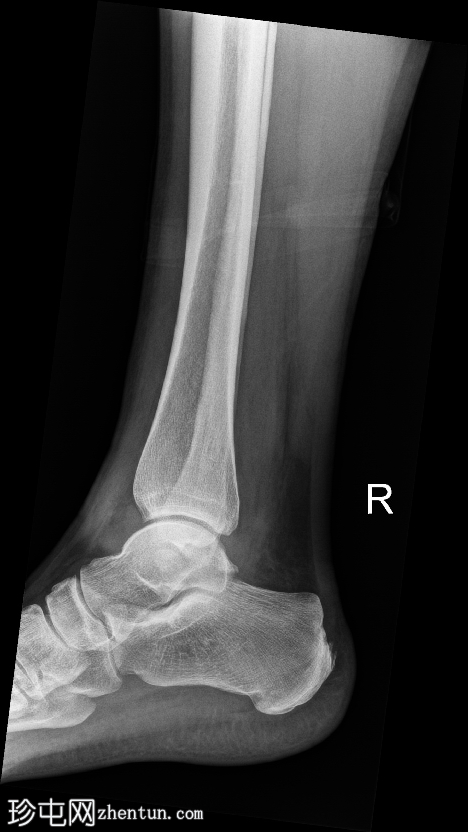

侧位片

腓骨远端下方可见一皮质完整的圆形小骨,符合腓骨下骨的特征。其光滑的边缘和皮质化程度提示为慢性副骨,而非急性撕脱骨折碎片。外踝上方可见局部软组织肿胀,表现为该区域软组织密度增高和隆起。

前后关节窝轻度扩张,提示踝关节积液。未见急性骨折或脱位。关节间隙清晰,对位正常。